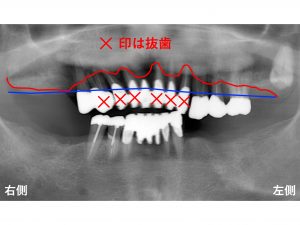

早速初診時のレントゲンから見ていきましょう!

前歯がグラグラして取れそうとのことで来院された患者様です。

検査の結果、

重度歯周病でした。

歯周病の進行はかなりの状態であり、

骨の吸収は相当進行していました。

骨吸収の状態を説明します。

本来の骨の位置が以下の青線です。

つまり骨吸収する前は、

ここまで骨があったということです。

それが、

歯周病が進行することで

以下の赤線まで

骨が溶けてしまったのです。

骨が吸収することで

歯がグラグラとなってしまったのです。

もう指で触れても歯が抜けそうな状態です。

とても食事ができる状態ではありません。

以下の×印の歯は抜歯となってしまいます。